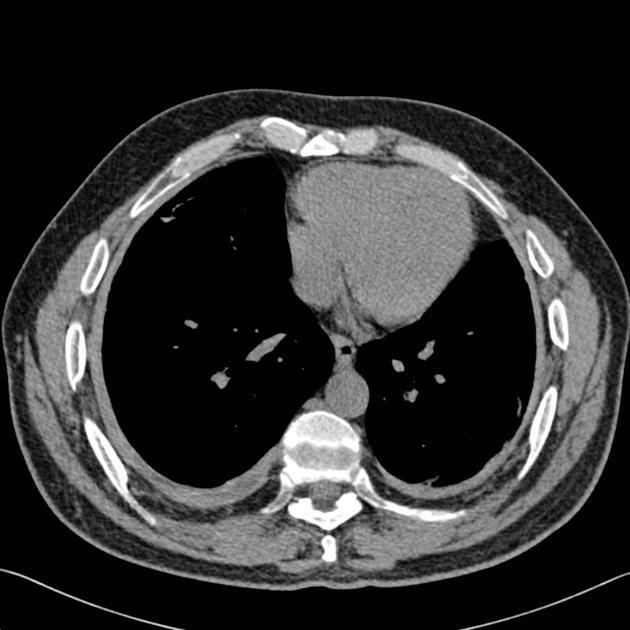

Espessamento e realce da pleura visceral e parietal separadas por derrame exsudativo/empiema.

Empiema, evienciando o split pleural sign.